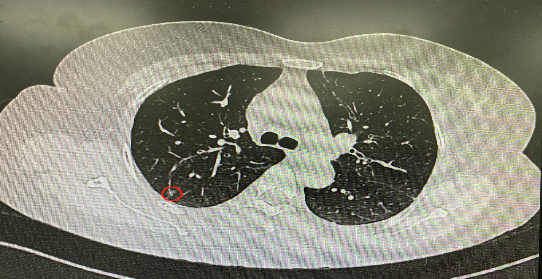

今年54歲的李女士(化名)7月初突然出現(xiàn)右上部腹痛,起初并未在意,以為稍作休息就會(huì)好轉(zhuǎn),但疼痛卻并未消退,持續(xù)了一個(gè)星期。李女士實(shí)在難以忍受,才在家人陪伴下來(lái)到西安國(guó)際醫(yī)學(xué)中心醫(yī)院就診。胸外科二病區(qū)崔凱主任接診患者后,詳細(xì)詢(xún)問(wèn)病情并查閱檢查資料,經(jīng)胸部HRCT檢查,結(jié)果提示:右肺上葉后段混合密度結(jié)節(jié)影,考慮原位癌可能,即將患者收入胸腔外科二病區(qū)住院治療。

經(jīng)與患者家屬溝通,崔凱主任決定行外科手術(shù)治療。為達(dá)到精準(zhǔn)切除,術(shù)前需進(jìn)行肺小結(jié)節(jié)切除前定位。由于結(jié)節(jié)位于右肺上葉后段,傳統(tǒng)經(jīng)胸外穿刺術(shù)無(wú)法抵達(dá)病灶。崔凱主任與呼吸內(nèi)科一病區(qū)歐陽(yáng)海峰主任討論后,決定擬行LungPro全肺診療導(dǎo)航下染色定位。即術(shù)前通過(guò)Lung Pro導(dǎo)航規(guī)劃染色位置,經(jīng)Lung Pro實(shí)時(shí)引導(dǎo)支氣管鏡抵達(dá)既定位置,注入亞甲藍(lán)染色劑標(biāo)記結(jié)節(jié)位置。

使用術(shù)前規(guī)劃系統(tǒng)重建全肺3D模型,并于外科醫(yī)生討論染色位置,最終確定標(biāo)記染色點(diǎn)—右肺上葉后段b亞段(RB2b)。術(shù)中使用P290(4.9mm外徑)標(biāo)準(zhǔn)支氣管鏡,根據(jù)導(dǎo)航術(shù)前規(guī)劃路徑,Lung Pro實(shí)時(shí)導(dǎo)航下,GS鞘管進(jìn)入RB2b遠(yuǎn)端官腔外病灶并注射亞甲藍(lán)染色劑。

一切準(zhǔn)備就緒,7月15日,崔凱主任團(tuán)隊(duì)聯(lián)合歐陽(yáng)海峰主任團(tuán)隊(duì)為患者行單孔胸腔鏡下右肺上葉后段切除術(shù),手術(shù)用時(shí)128分鐘順利完成。進(jìn)入胸腔后,亞甲藍(lán)染色部位明顯,患者發(fā)生癌變的右肺上葉后段被成功切除。術(shù)后標(biāo)本根據(jù)染色部位迅速找到結(jié)節(jié),剖開(kāi)位置兼染色位置和病灶完全符合,行術(shù)中冰凍后快速送病理檢查。經(jīng)術(shù)后病理檢查,明確診斷為(右肺上葉)原位腺癌。